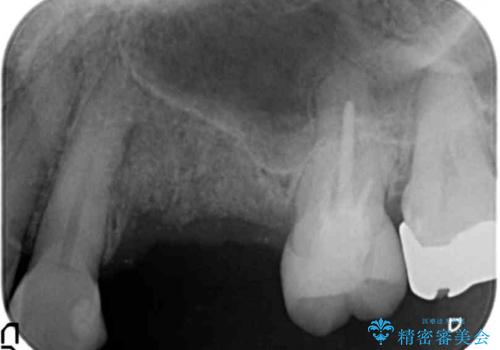

歯の穿孔(内部穴が開いている状態)破折等、歯を保存することができない問題が小臼歯には認められたので抜去を行います。

抜去後の補綴治療は長いブリッジではなくインプラント治療を希望されましたが、穿孔・破折による周囲の骨吸収をリカバリーすべく骨の造成を伴うインプラント治療を計画します。